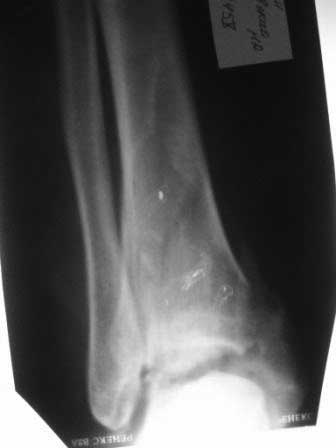

Есть ведь и перелом таранной кости? Не создаст ли он проблем с тенденцией к подвывиху? Нужно ли синтезировать таранную кость? Без КТ тут никак не обойтись.

Хоть вас и "интересует погружной синтез", тут надо аппаратом...

Конечно, после нормальной рентгенографии (что с тараном?). Кстати, первый снимок у меня вообще не открылся только боковой. В зависимости от сост-я тарана и решите, оперировать ли таран открыто, или просто фиксировать в АВФ.

Так был ли перелом тарана?

Здравствуйте! Покрутил на ЭОПе - похоже таран есть! - но трогать не стал - таран не оперируем - сил не хватает:):). Загипсовали.